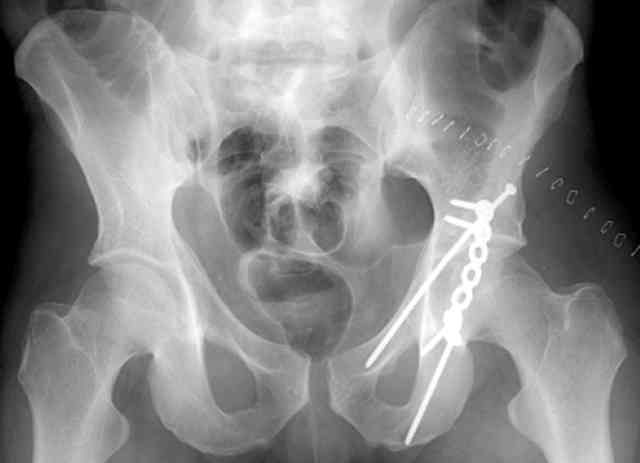

12.Prone Obturator-Outlet

Same with a contoured pelvic reconstruction plate applied and tensioned.

Prone Iliac Oblique

The other oblique reveals the extra-articular implants.... you know the AC screw is extra-articular from the other views.

Routine Fixation

AC Screw

PC Neutr Plate

Others

The unstable caudal segment is secured by the lower 2 plate screws and the AC medullary screw... always assure that your fixation is sufficient to defeat the instability... part of your prop plan... but assure it before you close... it¹s your last chance... you shouldn't have to be pushing on the hip in contorted ways to determine your fixation stability...you can if that makes you 'comfortable'.

A CT scan will rarely lie to you...reveals your reduction and implants...we use it to assess, teach, grade, and try to get better next time.